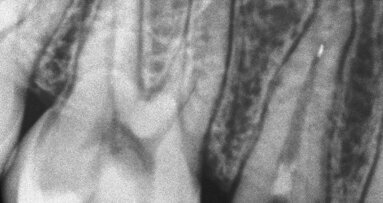

Pacijentkinja stara 32 godine došla je na pregled i konsultaciju oko nadoknade zuba 46 koji je izvađen mnogo godina ranije. Analizom ortopantomograma (sl.1) ustanovljena je obimna periapikalna lezija oko zuba 47 koji je trebalo da bude jedan od nosača buduće fiksne nadoknade. Pacijentkinja nije bila spremna na ugradnju implantata na mestu zuba 46.

Planiranje restauracije zuba je predstavljalo problem. Iako je zub imao očuvana četiri zida krunice (sl.2), pretpostavljeno je da bi se oni posle brušenja veoma istanjili ili potpuno nestali tako da smo se odlučili na primenu retencije unutar kanala korena. Međutim, prilikom uklanjanja prethodnog definitivnog punjenja kanala je utvrđeno da je ono u sebi sadržalo eugenol. Po mišljenju mnogih autora eugenolom kontaminirani kanal korena predstavlja kontraindikaciju za adhezivno cementiranje kočića ojačanih vlaknima. Iz tog razloga smo se odlučili za primenu metalnih kočića malog dijametra (NORDIN©, GOLD PLATED COMPOSITE SCREW POST), ali postavljenih u sva tri kanala. Na taj način smo maksimalno štedeli tkivo zuba i postigli dovoljnu retenciju kompozitnog materijala. Kočići su cementirani glas jonomer cementom (GC Fuji PLUS) koji je istovremeno predstavljao barijeru za prodor eventualno zaostalog eugenola iz kanala korena (sl.3). Tako su stvoreni preduslovi za uspešnu primenu dentin vezujućeg sredstva u kruničnom delu. Primenjeno je dvokomponentno samonagrizajuće dvostruko polimerizujuće dentin vezujuće sredstvo (GRADIA© CORE SELF-ETCHING BOND)(sl.4). Kod ovog sredstva nije potrebno nagrizanje i ispiranje tako da smo izbegli kvašenje glas jonomer cementa kojim su cementirani kočići. Želeli smo da budemo sigurni da je polimerizacija uspešno sprovedena i u dubokim delovima kaviteta, a i u onima koji su prilikom osvetljavanja led lampom ostali u senci metalnih kočića. Kao materijali za restauraciju su korišteni GRADIA© CORE ojačani kompozitni materijal za nadogradnje i G-enijal© Posterior (GC). Gradia CORE materijal je upotrebljen za popunjavanje kaviteta do nivoa na kome će se nalaziti okluzalna površina budućeg obrušenog patrljka(Slike 5 i 6). To je uradjeno zato što je to materijal koji je po svojim fizičko-hemijskim karakteristikama projektovan da može da bude zamenik za tkivo zuba na kome je planirana izrada krunice ili mosta. Drugi razlog je što je to materijal koji je dvostruko polimerizujući pa će sigurno biti polimerizovan i u delovima kaviteta do kojih svetlo polimerizacione lampe nedovoljno dopire. Treći razlog je što je njegova aplikacija iz kertridža sa mikrokanilom pogodna za primenu u kavitetu sa kočićima gde je teško postaviti materijale iz tube koji se štopuju nabijačima. Vrlo je važno da u restauraciji ne budu mesta koja su ispunjena vazduhom.